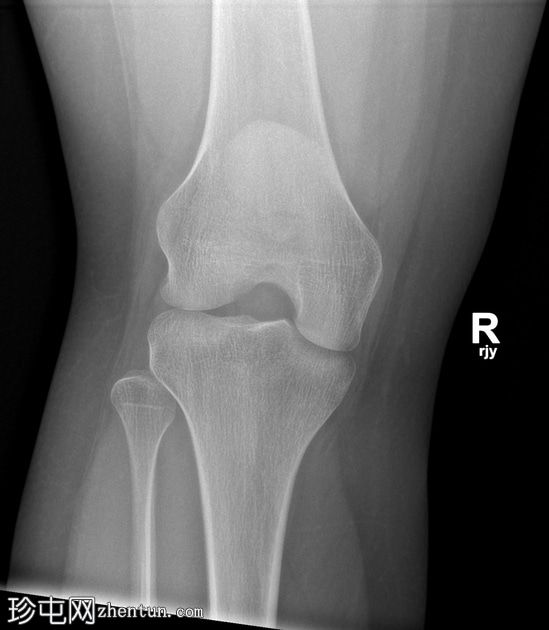

X光片

正面

髌骨下极横向骨折。髌腱影伴有软组织肿胀,提示创伤性髌腱炎。

髌骨撕脱性骨折通常发生在下极,属于关节外骨折。这类损伤最常见于青少年和年轻人,通常由膝关节突然过度屈曲引起。从生物力学角度来看,它们与髌腱断裂类似。